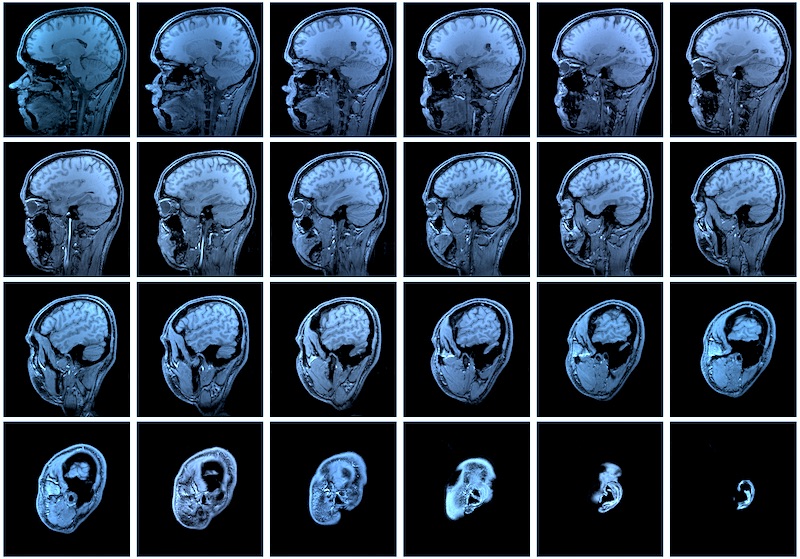

Három előre látható probléma van a CT- és MR-vizsgálatok átszervezésével: szükség lesz a gépekre, amiről ha sikerül megegyezni a magánszolgáltatókkal, akkor is 10 milliárdos tétel lehet, nem lesz egyszerű átcsábítani a radiológus asszisztenseket az állami rendszerbe, ahol jóval alacsonyabb fizetés várja őket és elvész a motiváció, hiszen az orvos ugyanannyit keres majd, mindegy hány leletet értékel – foglalta össze Rékassy Balázs, egészségügyi közgazdász a Reggeli gyorsban.

Államosítják a CT és MR vizsgálatokat, ami a költségvetési törvényhez utolsó pillanatban beadott módosításból derült ki, amivel megkerülték a szakbizottságot. Az orvosi kamara (MOK) szerint ez növelheti a várólistákat és ronthatja a gyógyulási esélyeket – számoltunk be a Népszava alapján.

Az elmúlt években számos kórházban – Budapesten például a Margitban, a Bajcsyban, a Péterfyben, a baleseti sebészetin – működtek együtt magáncégekkel. Ezek a cégek korábban beruháztak a diagnosztikai képalkotó eljárásokhoz szükséges felszerelésekbe és azt mondták a NEAK-nak (Nemzeti Egészségbiztosítási Alapkezelő), hogy ők hatákonyabban meg tudják szervezni ezeket a költséges eljárásokat a kórházakon belül. Ugyanazt a finanszírozást kapták, mint az állami vagy önkormányzati tulajdonú szolgáltatók. Érdekeltek voltak abban, hogy gyorsak, hatékonyak és profik legyenek, hogy csökkentsék a várólistákat, a radiológusok pedig minél több vizsgálatot tudjanak végezni, ez mindenkinek jó volt – magyarázta Rékassy, hozzátéve, ezért is tűnik értelmetlennek, hogy ebbe a kialakult rendszerbe nyúl bele a kormány, miközben az egészségügy ezer más sebből vérzik.

A távozó cégeknek felajánlhatják az államnak, hogy vegye meg tőlük a jellemzően 2-3 éves, korszerű eszközöket. Egy MR-gép kialakítása 300-500 millió forint, a CT pedig 100-200 millió között van. Ha meg tud egyezni a cégekkel az állam jobban jár, mintha teljesen új gépeket kellene beszerezni, kialakítani, de így is 10 milliárdos tétel lehet a felvásárlás – mondta a közgazdász. - Lesz-e, aki működtesse ezeket?